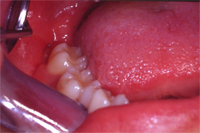

Abb. 3 zeigt die Situation direkt nach Entfernen des Zahnes. Die Wundheilung erfolgte absolut problemlos. Zwei Monate später ist kaum noch zu sehen, dass doch ein recht massiver zahnchirurgischer Eingriff stattgefunden hat (Abb. 4).